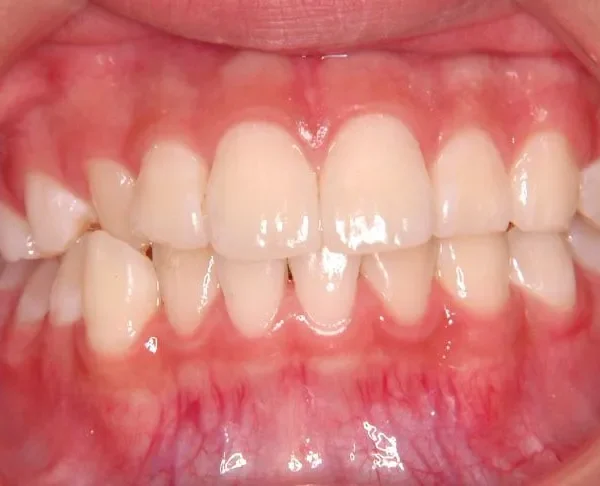

初診時

初診時年齢 小学校6年生 (女性) 主訴 犬歯がずれている・噛み合わない

診断名 叢生・交叉咬合 装置名

右下の犬歯がずれて生え噛み合わせの邪魔をしています。

歯は抜かず、上下マルチブラケット装置を使用し治療いたしました。

治療回数54回、9年3ヶ月の治療期間で矯正治療を終了しました。